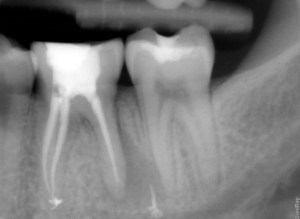

The moment I’ve been both dreading and looking forward to. This horribly painful pest of a root canal (see below) is finally getting the attention it has always wanted and I have been want to give. In a few hours, I am going to BIDC and getting this tooth retreated, hoping to save the tooth. If the tooth is not save-able, it’s implant time.

See broken filling and abscess (infection) on bottom right hitting nerves of tooth behind it. No fun, or in Thai, “mai sinook”.

Even though the total quote for BIDC was 47,000 as compared to 40,000, the dentist that I saw was remarkable holistic and was an expert in root canals. Immediately she saw my X-Ray and said that I had enough bone structure to save the tooth and that it is always better to save the natural tooth. Any dentist who is trying to make money off you will tell you to go for the implant, because it is a much more expensive procedure.